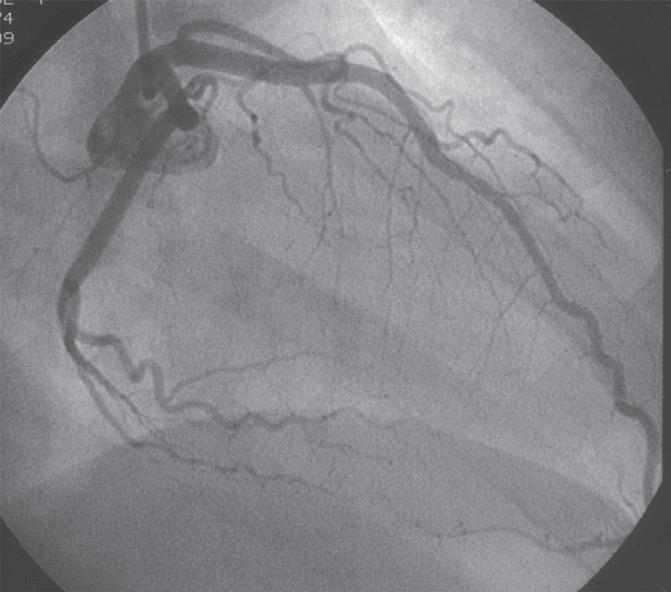

Figura 18.36 – Angiografia da artéria coronária direita. Visualização das diversas colaterais. A. Oblíqua anterior esquerda 45º caudal 15º; B. Oblíqua anterior direita 45º.

Figura 18.37 – Coronariografia da artéria coronária direita (dominante).